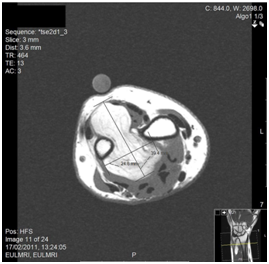

An 81year-old lady presented with gradually enlarging masses in the thenar area, first webspace dorsum and along the flexor tendons of the left hand. Global left hand pain which disturbed sleep was noted, with pincer grip weakness. The medical history included controlled hypothyroidism, hypertension and hypercholesterolaemia. MRI demonstrated a thenar eminence lesion (Figure 1), extending across the flexor tendons in the palm and forearm. Appearances were inconsistent with giant cell tumours or chronic synovitis. High fat content and gadolinium enhancement raised the possibility of liposarcoma. An ultrasound guided biopsy demonstrated benign adiposeand fibrous tissue. The hand was explored under general anaesthetic. Upon opening the carpal tunnel, multiple lipomatous lesions were present along the full extent of the flexor sheath (Figure 2). Each was excised with attached synovial tissue, similar to a rheumatoid synovectomy. A Y-shaped extension of the palmar incision, with division and ligation of the superficial palmar arch, provided access to deeper lesions. Synovial lipomatosis infiltrated the lumbricals and surrounded the flexor tendons. All branches of the median nerve were decompressed. Local anaesthetic was infiltrated and a double lumen Yates drain was placed. Histopathology confirmed benign adipose tissue with fibrovascularstroma and spindle cells. At one month, the wound had healed and finger flexion was full, with resolution of the neuropathy and no recurrence at eight months.

Figure 1 Coronal, sagittal and axial MR images of the left hand, showing lipomatous infiltration around the flexor tendons, and thenar mass.